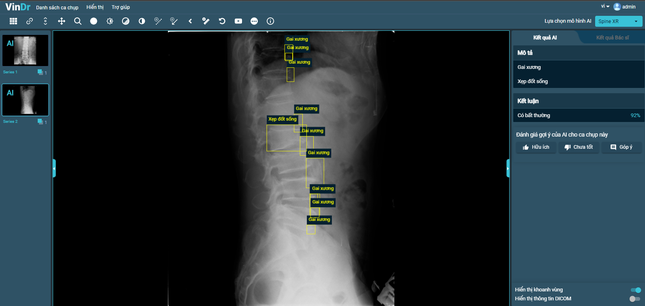

After more than a year of ceaseless efforts, VinBigdata has successfully developed a new module for interpreting spine X-ray images. It can detect 6 types of common lesions in Vietnam, including: osteophytes, disc space narrowing, surgical implant, foraminal stenosis, spondylolisthesis and vertebral collapse, with accuracy rate of 90%.